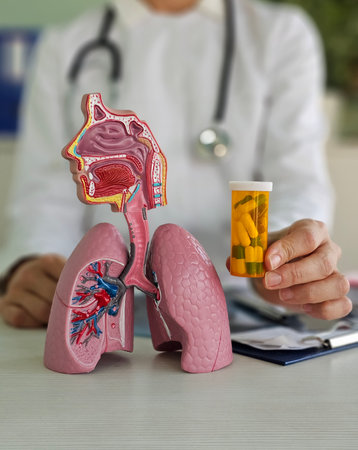

Medical model of human respiratory system displayed during consultation with doctor in clinic

Human respiratory system showing lungs and trachea placed on a desk near educational materials

Medical professional demonstrating lung anatomy and medication in a health clinic setting